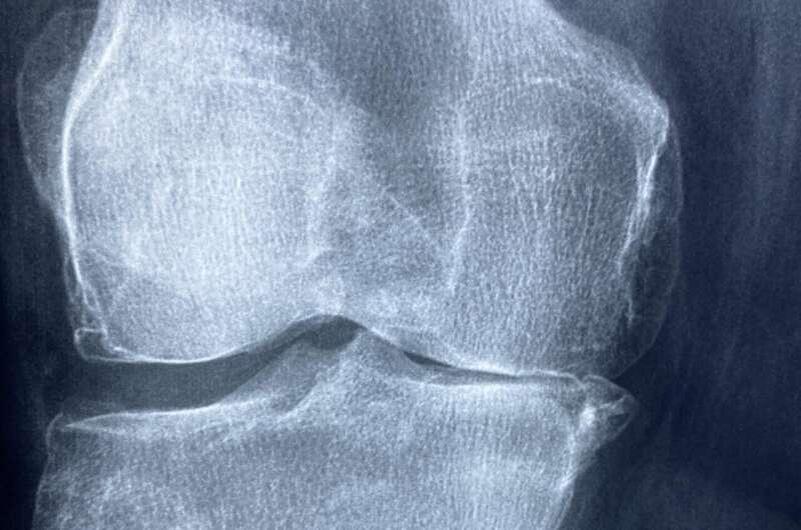

Исследователи из Школы стоматологии в Рибейран-Прету при Университете Сан-Паулу (FORP-USP) в Бразилии обнаружили, что белок агрин играет важную роль в сохранении костной массы и качества костей. Это открытие может изменить наше понимание поддержания здоровья костей и проложить путь к новым методам лечения заболеваний костей, включая остеопороз.

Мыши без агрина в остеоцитах показали значительное уменьшение костной массы, а также физические и химические изменения в составе костей. Эти изменения нарушали структуру ткани, делая кости более хрупкими и склонными к переломам.